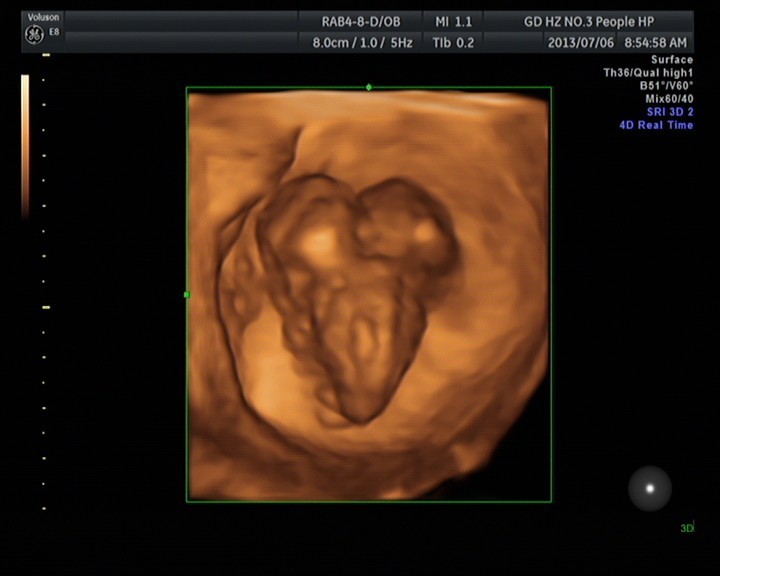

随着环境污染日益严重,随着各种地沟油的诞生,随着各样镉大米的泛滥……我们的健康越来越受到威胁,很多疾病也随之接踵而至,胎儿先天性疾病也越来越多见。7月6日,我院超声科王瑶医生在做胎儿产前NT筛查中发现一例孕约11周+的联体双胎。超声所见:增大的子宫内可见联体双胎儿回声,可见两个胎头不能分离,胸部及腹部融合,可见一个增大的心脏。

联体婴儿B超图像